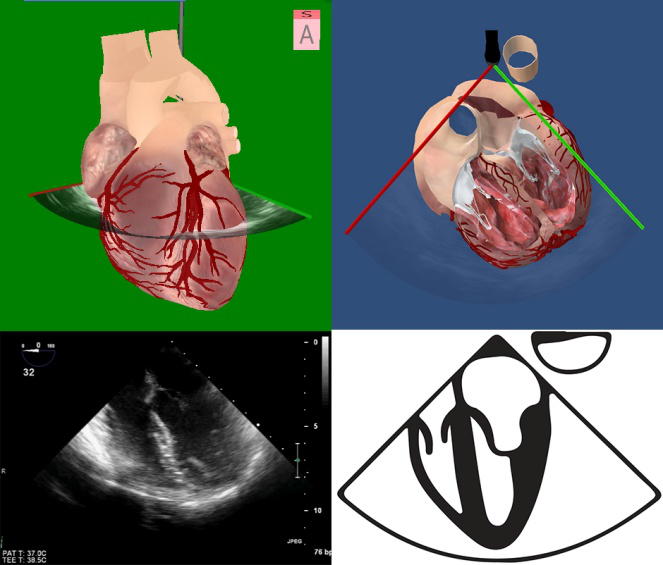

图2 2D和3D图像及成像原理 图3食管中段4腔心切面及模型图

2D或是3D图像(图2)都需要定义视角,采取面对心脏模型的视角,有2个理由:①面对心脏模型与系统解剖学方位一致,便于沟通;②面对心脏模型有利于实现从TEE到TTE的快速切换。以食管中段4腔心切面为例,描述探头与图像的位置关系理解图像和心脏模型的位置关系(图3),直观地显示了探头、切面与心脏模型的空间关系。